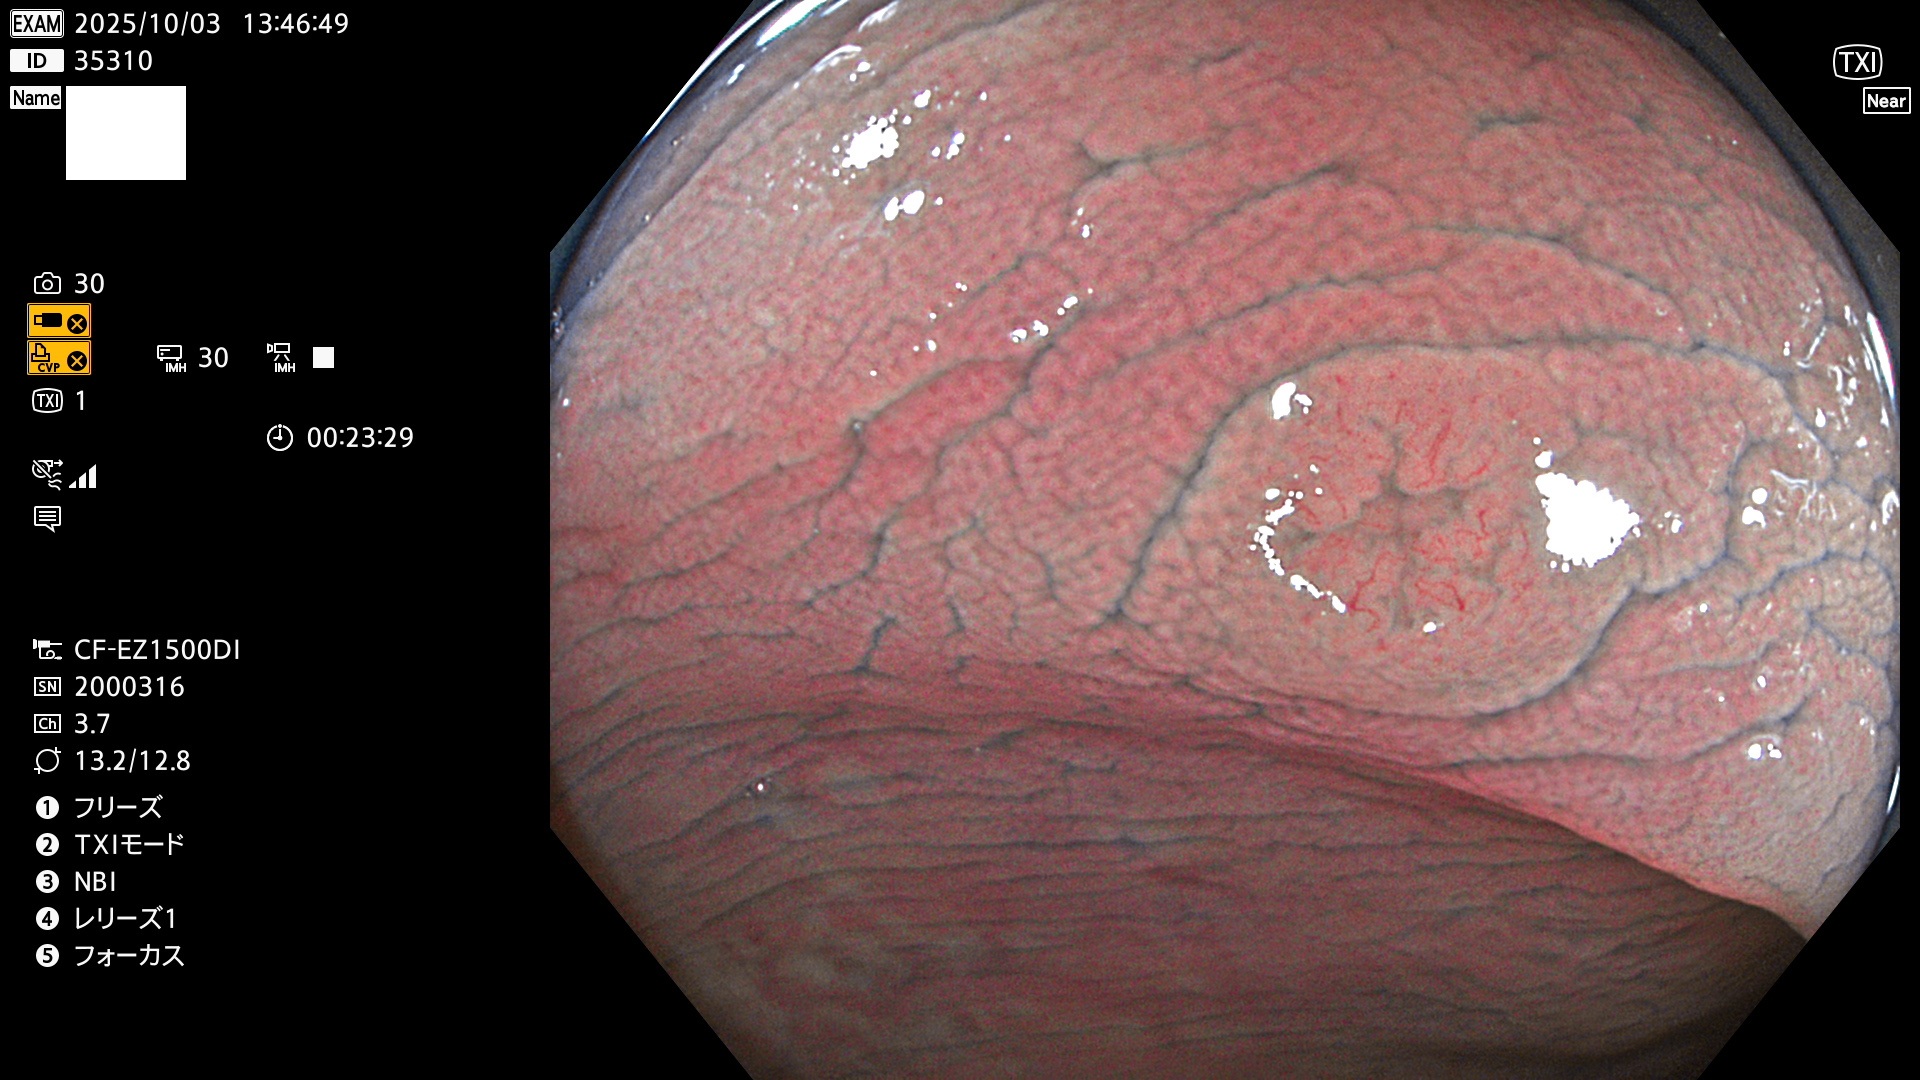

完全に平坦な物をUb、陥凹している物をUcと呼びます。Ubは認識が困難で、Ucはびらん(炎症)と紛らわしいために見落とされやすく、「内視鏡後・大腸癌」の原因になります。

専門的)Uc=De Novo癌? 内視鏡の解像度が低かった時代、このような説もありました。しかし今日の高精度内視鏡では良性の微小なUc型腺腫(APC遺伝子異常の腺腫)が日常的に見つかります。Ucこそが多段階発癌(Adenoma-Carcinoma Sequence)のMain Routeです。

毎週の検査(木・金・土・日)に発見されたUbとUc型・腺腫を、その週の日曜の夜にUPし1週間、提示します。